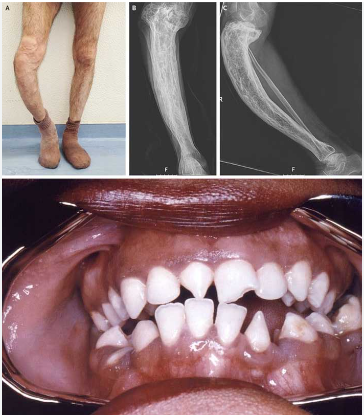

• Pseudoparilisa de Parrot: limitação de movimento unilateral de MMSS devido a osteocondrite

• Alterações radiográficas:

1. Periostite:

2. Sinal de Wimberger: degeneração da porção proximal da tíbia

Principais:

• Dentes de Huntchington

• Tíbia em sabre